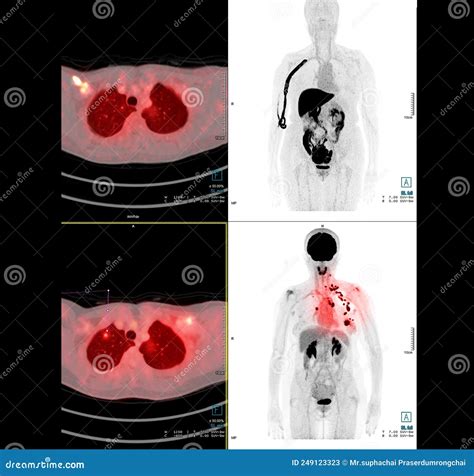

In the realm of medical imaging, the Pet Scan Image stands out as a powerful tool for diagnosing and monitoring various diseases. Positron Emission Tomography (PET) scans use radioactive tracers to produce detailed images of the body's internal structures and functions. These images provide invaluable insights into metabolic processes, making them particularly useful in oncology, neurology, and cardiology.

A Pet Scan Image is created by injecting a small amount of radioactive tracer into the body. This tracer emits positrons, which collide with electrons in the body, producing gamma rays. The PET scanner detects these gamma rays and constructs a three-dimensional image of the body's internal activity. The resulting images highlight areas of high metabolic activity, which can indicate the presence of disease.

• Oncology: PET scans are widely used to detect and stage cancer. They help identify cancerous tumors and determine the extent of the disease, aiding in treatment planning.

Interpreting Pet Scan Images requires specialized training and expertise. Radiologists and nuclear medicine physicians analyze the images to identify areas of abnormal metabolic activity. The interpretation process involves:

• Comparing the PET scan images with other imaging modalities, such as CT or MRI scans, to provide a comprehensive view of the body's structures and functions.

For example, in oncology, areas of high metabolic activity on a Pet Scan Image may indicate the presence of cancerous tumors. In neurology, abnormal patterns of tracer uptake can help diagnose conditions like Alzheimer's disease or epilepsy.

• Hybrid Imaging: Combining PET with other imaging modalities, such as CT or MRI, provides a more comprehensive view of the body's structures and functions. Hybrid imaging systems, like PET/CT and PET/MRI, offer improved diagnostic accuracy and treatment planning.